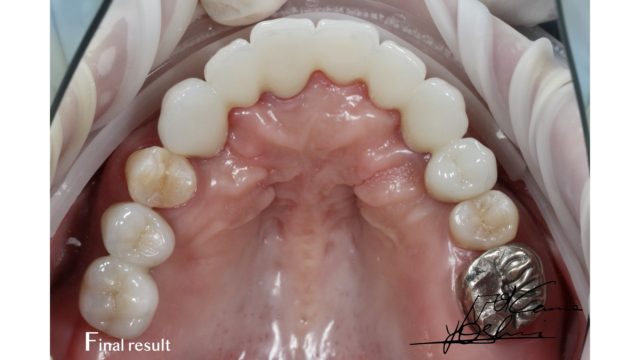

お口の上部、AFTER写真です。